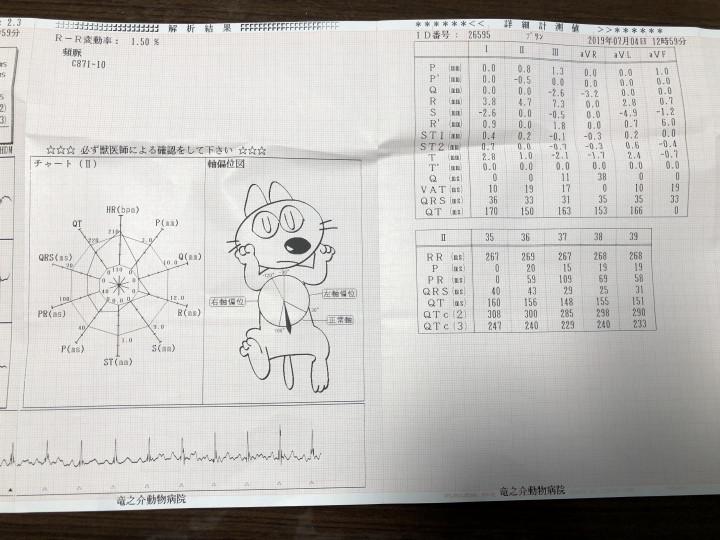

心電図取りました。

不整脈は出ていません。

心筋の厚さも基準値内でした。

コレも確認してください。特に

今のところ問題はないようです。